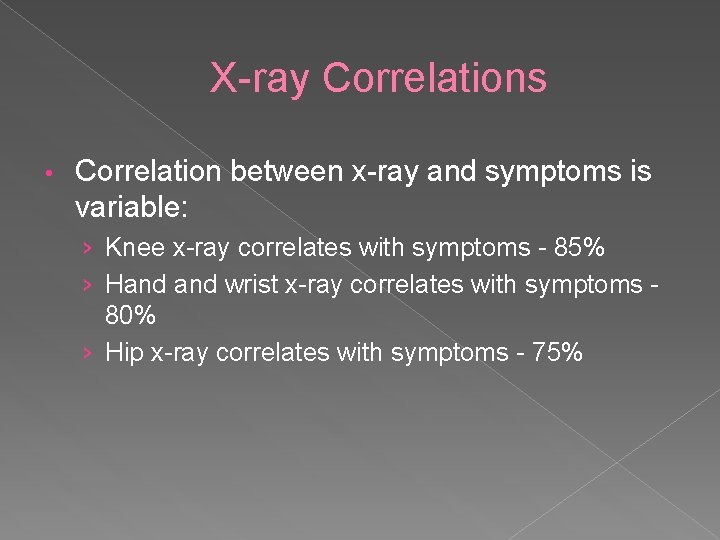

X-ray Correlations • Correlation between x-ray and symptoms is variable: › Knee x-ray correlates with symptoms - 85% › Hand wrist x-ray correlates with symptoms - 80% › Hip x-ray correlates with symptoms - 75%